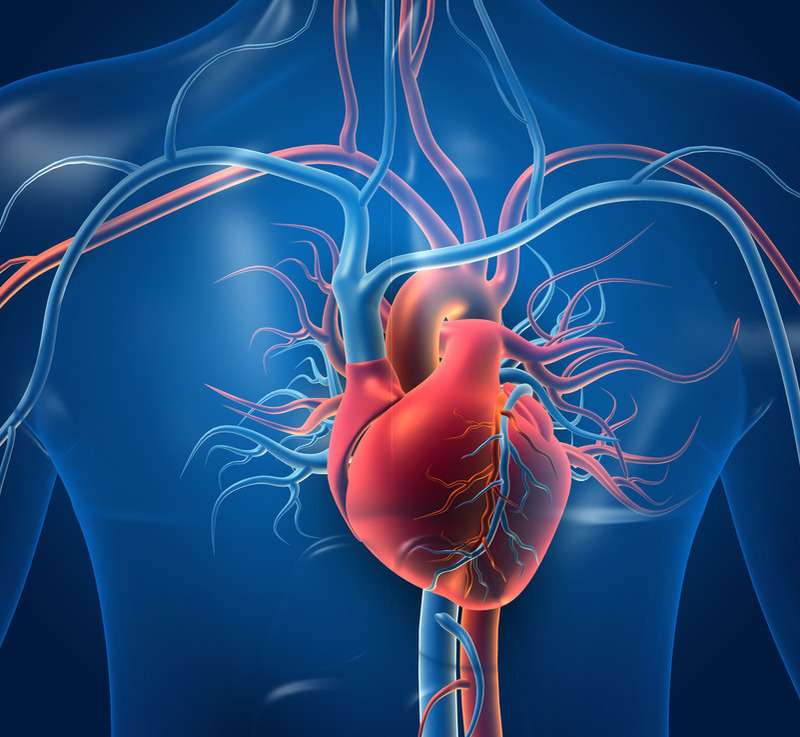

Sydän- ja verisuonitaudit

Kardiologia on lääketieteen tieteenala, joka keskittyy diagnosoimaan ja hoitamaan sydän- ja verisuonisairauksia, jotka vaikuttavat sydämeen, verisuoniin ja verenkiertoelimistöön. Näihin vaivoihin kuuluvat sepelvaltimotauti (sydänverisuonten sairaus), sydämen rytmihäiriöt (epänormaali syke), sydämen vajaatoiminta (sydän ei kestä työtaakkaa), kohonnut verenpaine (hypertensio), kardiometabolinen sairaus (joukko sairauksia, joihin liittyy sydän ja aineenvaihdunta), rasva-aineenvaihdunnan häiriö (epäsäännölliset veren lipidipitoisuudet), sydänläppäsairaus ja kardiomyopatiat (sydänlihassairaudet).